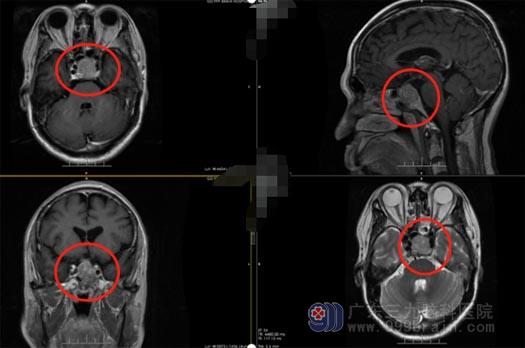

67岁的刘大叔3年前开始出现反复的头晕;1个月前,不但头晕没有好转还伴有头痛加重。近几日,刘大叔的视力开始模糊,他和家人都十分担心,在家属的陪同下,他们来到广东三九脑科医院,头颅MR检查提示:垂体大腺瘤可能性大。

垂体瘤是一种常见的生长缓慢的良性肿瘤,垂体瘤的手术大致分为开颅垂体瘤切除和经鼻蝶垂体瘤切除术两种。随着显微外科的发展,经鼻蝶垂体瘤切除术成为首选手术方法,既能切除肿瘤又完好保存垂体功能,手术和麻醉时间短,并发症少,恢复快,死亡率低,能够避开开颅对额叶,嗅神经,视神经的破坏。